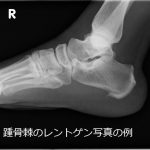

踵骨棘の改善経過